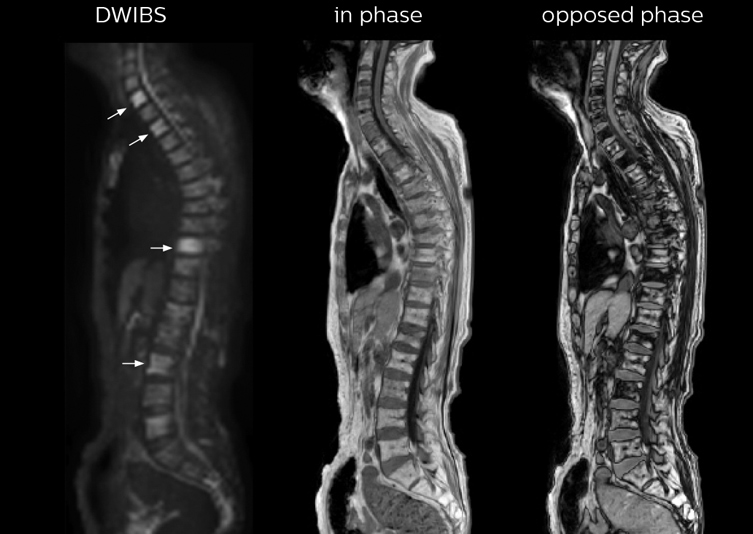

“In-phase and out-phase sagittal T1-weighted FFE images help us to visualize and further characterize bone lesions such as metastasis and bone-marrow hyperplasia that have high signal on DWI. These images are also used throughout radiotherapy, to monitor changes in the fatty bone marrow.”

The single shot T2-weighted TSE images are used for morphology and compared to DWIBS images to identify T2 shine-through. Sagittal STIR images are used in patients with inflammation or bone metastasis.

Kawasaki Sawai Hospital’s whole body protocol also includes an mDIXON FFE sequence. Because mDIXON provides images for four contrast types – water only, fat only, in-phase and out-of-phase – from a single acquisition, it is useful in many ways.

“mDIXON FFE allows us to quickly get information we need to assess the presence of fat. That gives us more information when we need to diagnose bone lesions, and when we are asked to judge fat-containing lesions such as hepatocellular or renal carcinoma,” Dr. Nobusawa says.

“The mDIXON fat images can help us to differentiate fatty bone marrow from bone lesions. This is especially useful in elderly people, who tend to have fattier bone marrow. The water images provide a high signal-to-noise ratio in the intestinal canal, which is valuable for visualizing lesions in the colon,” he says.